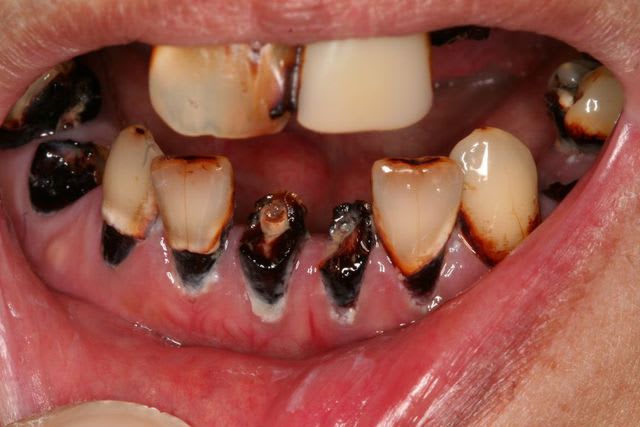

Collaverdey

JH, 40 ans,

motif de consult: sa femme ne veux plus l'embrasser ...